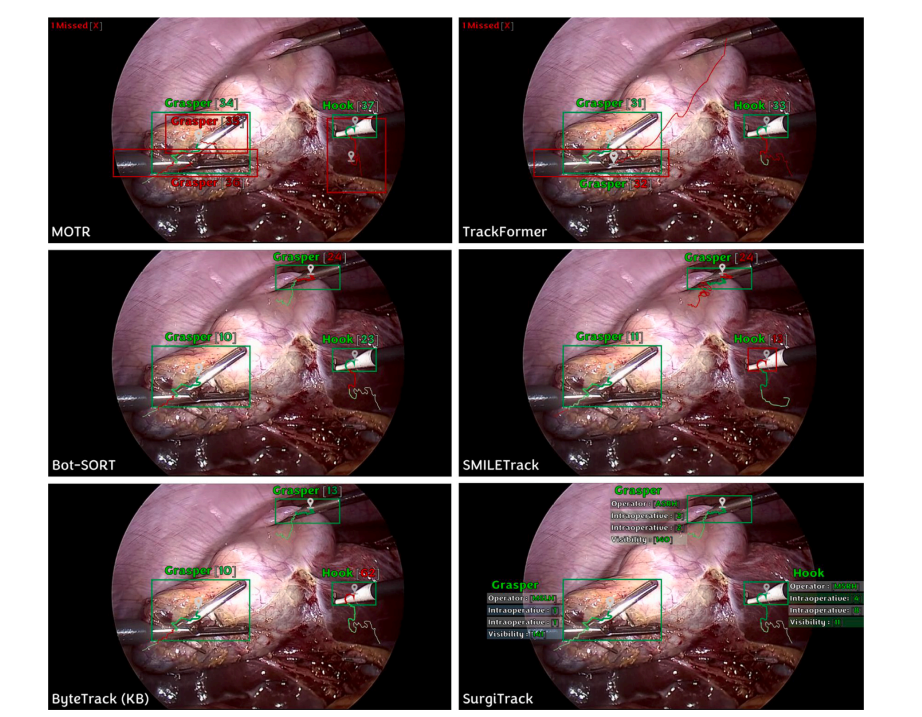

Fig. 6. Qualitative result of SurgiTrack in comparison with some existing methods. Bounding box represents tool detection, tool name represents tool classification, number inblock parenthesis represents track identity, and scribble represents tracklet (max. 2 s). Green color indicates correctness, red indicates failure. A demo is included in the qualitativeresults video.

图 6. SurgiTrack 与一些现有方法的定性比较结果。 矩形框表示器械检测结果,器械名称表示器械分类,括号中的数字表示轨迹身份,线条表示轨迹片段(最长 2 秒)。绿色表示正确,红色表示失败。 定性结果视频中包含演示。